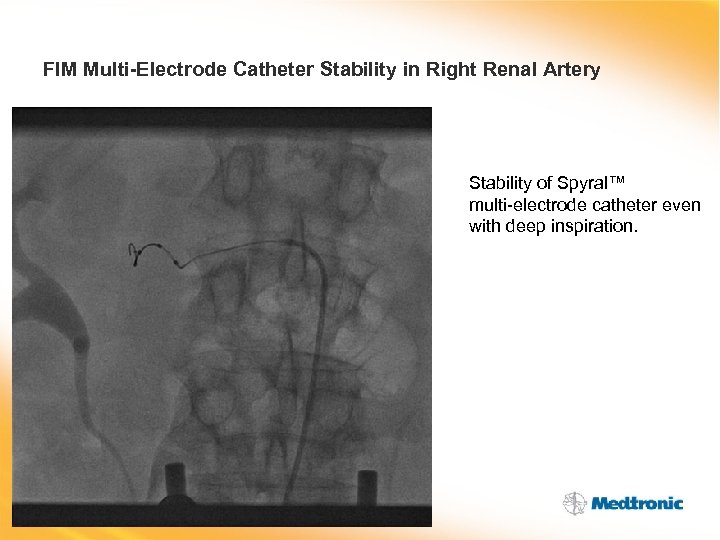

FIM Multi-Electrode Catheter Stability in Right Renal Artery Stability of Spyral™ multi-electrode catheter even with deep inspiration.

FIM Multi-Electrode Catheter Stability in Right Renal Artery Stability of Spyral™ multi-electrode catheter even with deep inspiration.